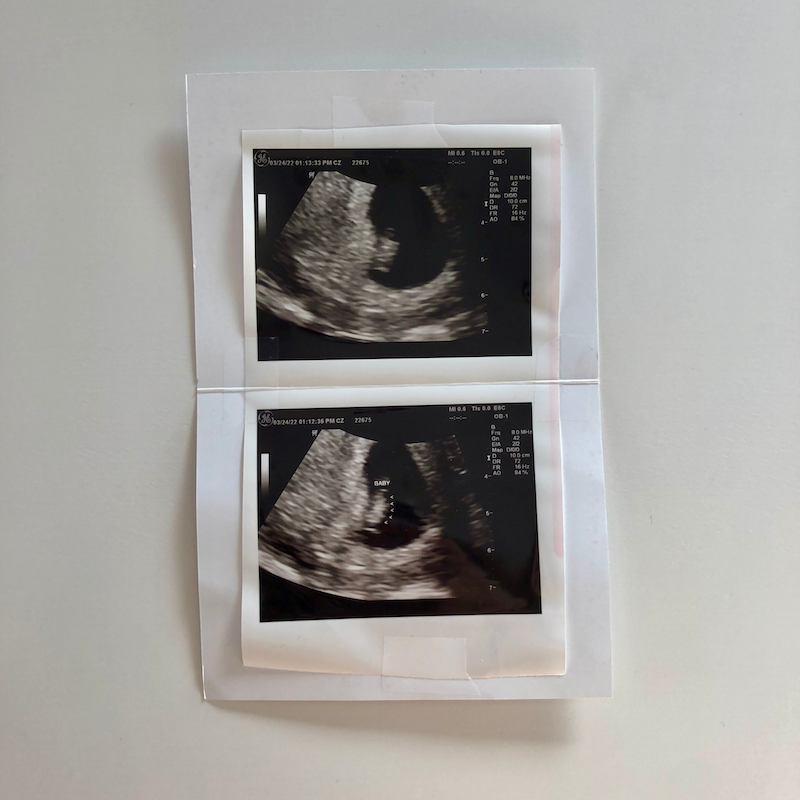

I have some very exciting news to share today! This is a post I’ve been looking forward to writing for some time. We are expecting a baby in November!

8 week ultrasound